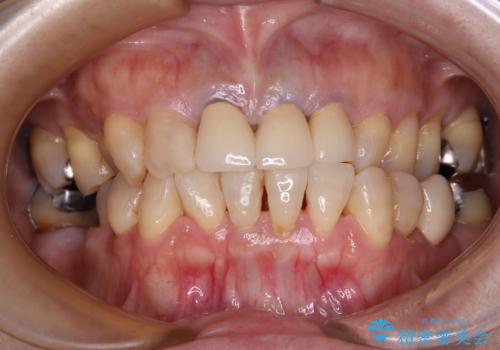

透明感のある自然な色合いとなり、患者様には大変満足していただけました。